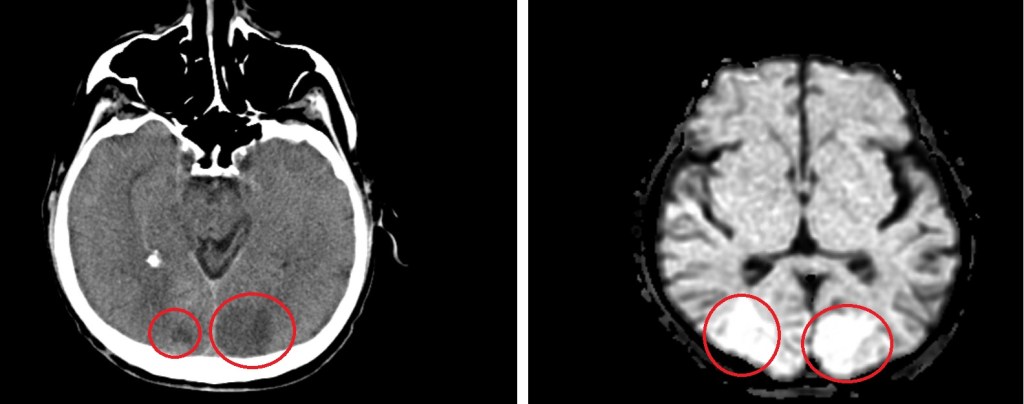

Posterior reversible encephalopathy syndrome (PRES) is a clinico-radiological syndrome characterized by a headache, seizures, altered mental status and visual loss and characterized by white matter vasogenic edema affecting the posterior occipital and parietal lobes of the brain predominantly | source: https://www.ncbi.nlm.nih.gov/

left: CT non contrast | right: MRI brain